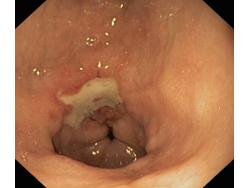

Wrzód trawienny